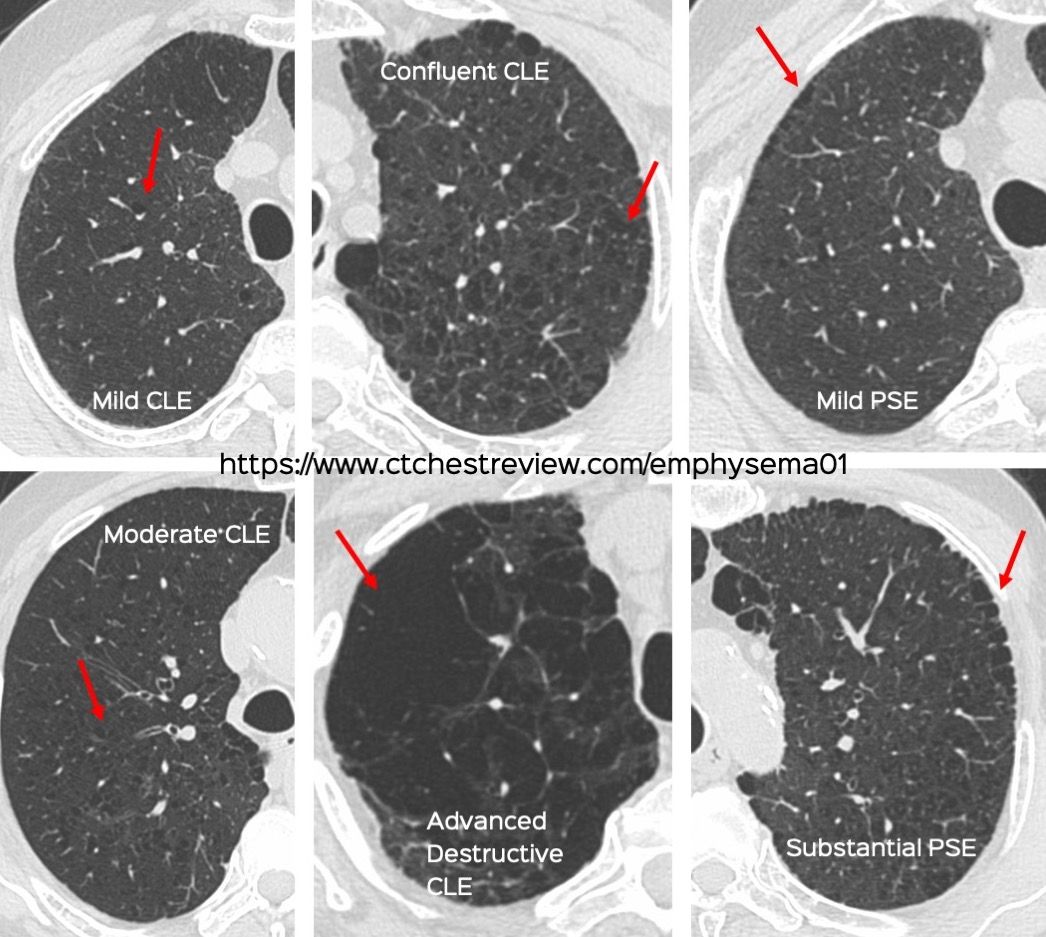

The official research statement on combined pulmonary fibrosis and emphysema (CPFE) was published last week. It has definitions to help us diagnose CPFE from a research perspective as well as clinically.

The video explains the salient features of the statement using a 69-years old 50-pack years smoker as an example.